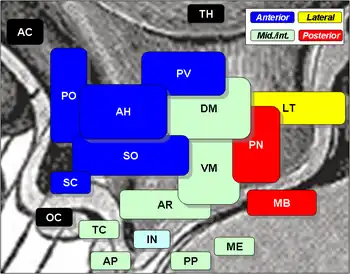

Neurokinin B (NKB) belongs in the family of tachykinin peptides. Neurokinin B is implicated in a variety of human functions and pathways such as the secretion of gonadotropin-releasing hormone.[1] Additionally, NKB is associated with pregnancy in females and maturation in young adults. Reproductive function is highly dependent on levels of both neurokinin B and also the G-protein coupled receptor ligand kisspeptin.[2] The first NKB studies done attempted to resolve why high levels of the peptide may be implicated in pre-eclampsia during pregnancy.[3] NKB, kisspeptin, and dynorphin together are found in the arcuate nucleus (ARC) known as the KNDy subpopulation. This subpopulation is targeted by many steroid hormones and works to form a network that feeds back to GnRH pulse generator.[4]

During the ovarian cycle, GnRH secretion along with that of luteinizing hormone (LH) is highly regulated. This regulation occurs by a negative feedback system. Neurokinin B along with its sister peptides of the KNDy subpopulation regulate this feedback. The NK3R receptor group when activated with a synthetic agonist of NKB, senktide, has been shown to stimulate the secretion of luteinizing hormone.[4] In addition, studies have shown that NKB plays a larger role in females than in males. It has been found that in brain of females, the arcuate nucleus contains twice as many connections to NKB neurons than males.[1]

The main receptor neurokinin B interacts with is the neurokinin 3 receptor (NK3R).[6] The Neurokinin 3 receptor is a part of a larger family of G-protein coupled receptors that binds all tachykinin proteins. While neurokinin B has the ability to bind to other Neurokinin receptors, the highest affinity lies in that of the NK3R receptor group.[6] Much like the neurokinin B peptide, the NK3R receptor that it binds to is encoded within five exons of the TACR3 gene in humans and the Tacr3 gene in mice and other rodents.[6] High concentrations of the NK3R receptor are found in both the central nervous system and the spinal cord. Additional NK3R receptors have also been found in various other places in the body including: uterus, mesenteric vein, gut neurons, and placenta.[6] Neurokinin B has also been found to co-localize certain gonadal steroid hormone receptors. These include the estrogen receptor (ERα), progesterone receptor (PR), and androgen receptor. It has been found that co-localization of the NKB neurons near these receptors is at a much higher concentration than even that of other peptides and chemicals. The kisspeptin, neurokinin B, and dynorphin cell groups are found to be co-localized to more than 95% of all of the aforementioned receptors in the arcuate nucleus.[4]

Role of gonadotropin-releasing hormone

Mutations or defects in the TAC3 or TAC3R gene can lead to steroidal feedback problems in the GnRH pulse generator loop, causing GnRH to be understimulated. Lack of GnRH ultimately leads to hypogonadism.[4] A review of neurokinin B and its sister peptides, kisspeptin and dynorphin, in sheep found that these KNDy cell groups (kisspeptin, neurokinin B, dynorphin), are in direct contact with the GnRH neuronal bodies in both the preoptic area and the mediobasal hypothalamus. Researchers found this to be feature to be conserved among species including humans.[4] Due to the high percentage of co-localization found with neurokinin B cell bodies and receptor groups, it is suggested that Neurokinin B along with kisspeptin and dynorphin play a role in the release of GnRH.[4] These findings are important since GnRH release plays such a pivotal role in regulating hormonal control in the bodies of humans.

Along with rats, primate studies have been done, investigating the effects of NKB and the other peptides of the KNDy subpopulation. Due to the similarity in brain structure monkeys have been good research candidates. In humans, as previously mentioned, NKB signaling plays a vital role in hormone secretion, especially that of luteinizing hormone before the onset of puberty. It was shown, in monkeys, that activation of NK3R, the NKB receptor, was associated with release of hormones that come before the onset of puberty. This included initial release of GnRH. NKB found mostly in the arcuate nucleus in humans, is found mostly in the monkey hypothalamus. By injecting NKB analogs pulsatile GnRH was secreted, activating the hypothalmic-pituitary axis and therefore releasing LH. Researchers found these results consistent across both monkey and human brains.[11]